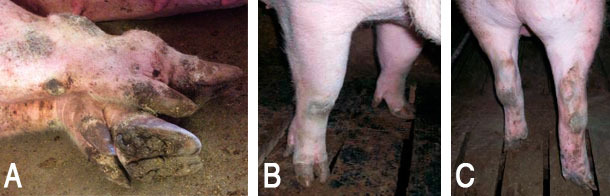

Exemples de lésions des extrémités : A) inflammation des extrémités et abcès, B) callosité du carpe, C) bursite et callosité du tarse.

Exemple de lésions des onglons; A) surcroissance des onglons et ergots et B) ergots amputés.